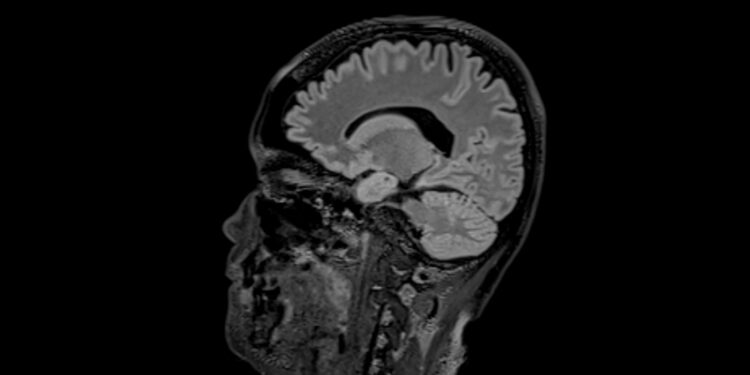

Dalis genetinių pakitimų veikia ir uoslę: normaliomis sąlygomis uoslės nervų ląstelės siunčia signalus uoslės svogūnėliui, tačiau sergant šiuo sindromu tie signalai smegenų nepasiekia, todėl žmogus nejaučia kvapų. Jeigu šio pojūčio netrūksta, būklė vadinama normosminiu idiopatiniu hipogonadotropiniu hipogonadizmu.